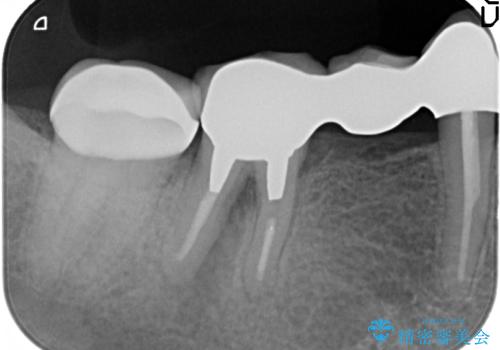

その後右下5、6番目にはインプラントを埋入し、右下3、4、5、6、7番の歯の補綴をオールセラミッククラウンによって行いました。

- オールセラミッククラウン…¥100,000×5、仮歯…¥10,000×5、インプラント(ストローマン)…¥200,000×2、カスタムアバット…¥100,000×2、骨増生…¥50,000費用は治療当時の料金となります

今回用いたオールセラミッククラウンはジルコニアフレームという白い素材の上にセラミックを盛っているため、審美性が非常に高いのが特徴です。

また、ジルコニアは人工ダイヤモンドの材料にも使われているほど高い強度を持っており、そのためオールセラミッククラウンは審美性だけでなく、奥歯やブリッジの補綴も可能とするクラウンです。